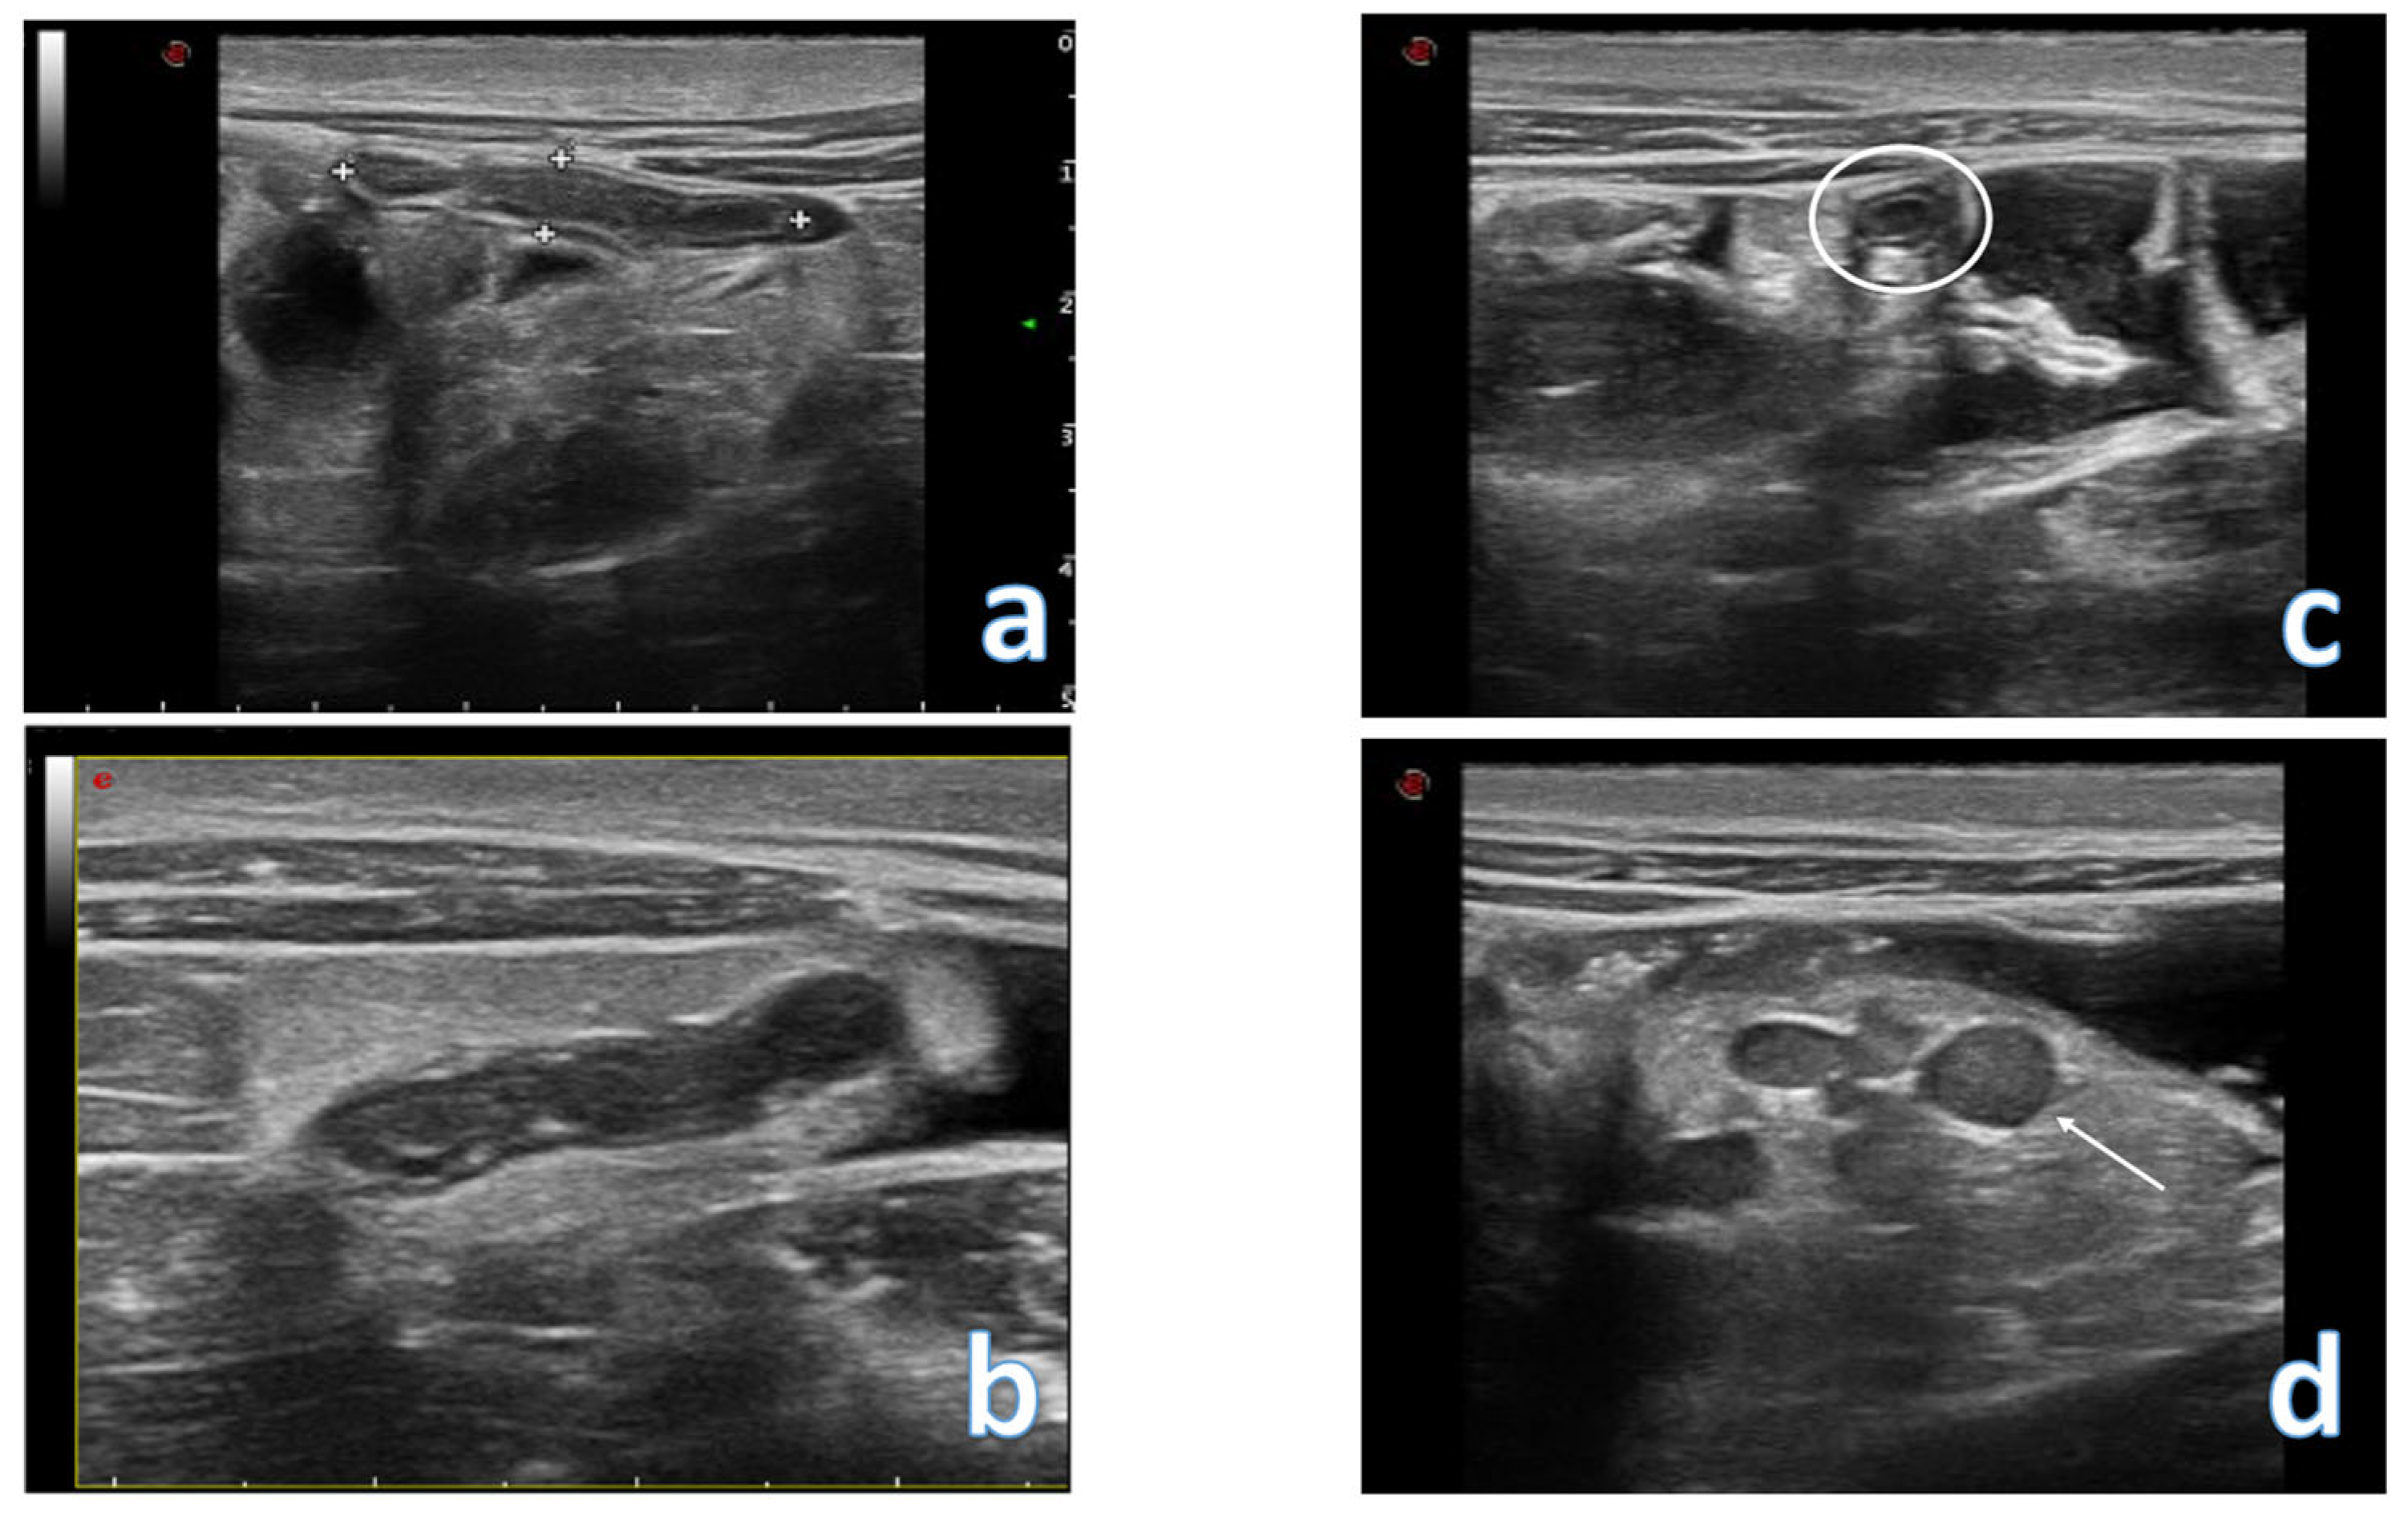

4. Acute Appendicitis

5. Acute Diverticulitis

- Quigley, A.J.; Stafrace, S. Ultrasound assessment of acute appendicitis in paediatric patients: Methodology and pictorial overview of findings seen. Insights Imaging 2013, 4, 741–751. [Google Scholar] [CrossRef] [PubMed]

- Park, N.H.; Oh, H.E.; Park, H.J.; Park, J.Y. Ultrasonography of normal and abnormal appendix in children. World J. Radiol. 2011, 3, 85–91. [Google Scholar] [CrossRef] [PubMed]

- Atema, J.J.; van Rossem, C.C.; Leeuwenburgh, M.M.; Stoker, J.; Boermeester, M.A. Scoring system to distinguish uncomplicated from complicated acute appendicitis. Br. J. Surg. 2015, 102, 979–990. [Google Scholar] [CrossRef] [PubMed]

- Rawolle, T.; Reismann, M.; Minderjahn, M.I.; Bassir, C.; Hauptmann, K.; Rothe, K.; Reismann, J. Sonographic differentiation of complicated from uncomplicated appendicitis. Br. J. Radiol. 2019, 92, 20190102. [Google Scholar] [CrossRef] [PubMed]